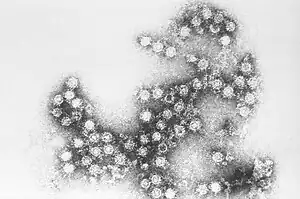

| Coxsackie B virus-the most common cause of Bornholm disease | |